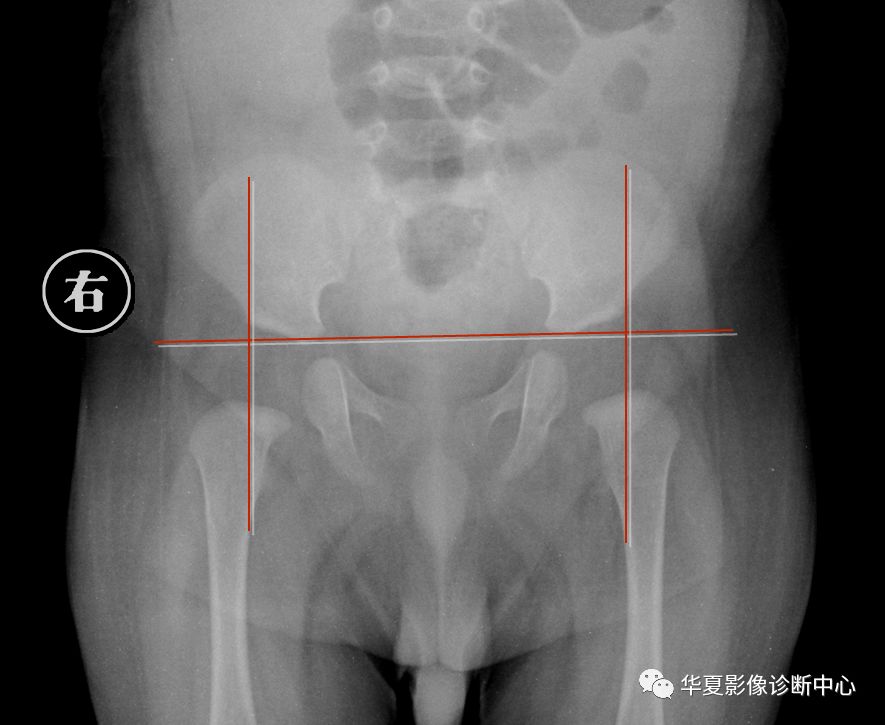

4.髋臼指数

从髋臼外缘向髋臼中心连线与H线相交形成的锐角,称为髋臼指数。

出生时,髋臼指数为25.8°~29.4°,6个月婴儿19.4°~23.4°,2岁以上者在20°内。

当小儿步行后此角逐年减小,直到12岁时基本恒定于15度左右。大于正常值者说明臼顶倾斜度增加,为髋臼发育不良。多数学者认为超过30°就有明显脱位趋向。

5.CE角

也叫中心边缘角(center edge angle),即股骨头中心点与H线的垂线,髋臼外缘与股骨头中心点的连线所形成的夹角。

其意义是检测髋臼与股骨头相对的位置,对髋臼发育不良或半脱位有价值。

此角正常范围为20°~46°,平均35°。15°~19°可疑;小于15°甚至负角,表示股骨头外移,为脱位或半脱位。